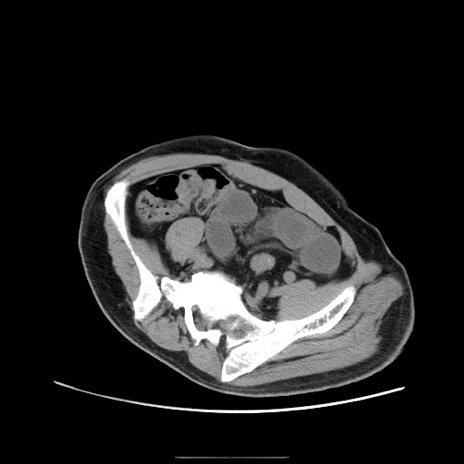

症例

冠状断像